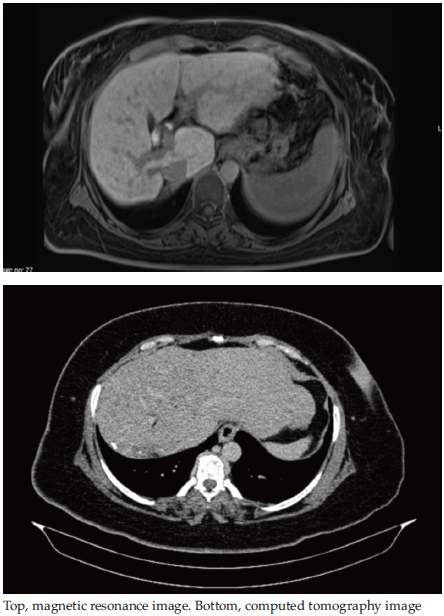

The HBV DNA polymerase chain reaction results revealed a viral load of 2290000 IU/mL. The patient’s laboratory test results are shown in Table 1. Magnetic resonance images and dynamic computed tomog-raphy images showed signs of chronic liver disease, including hypertrophy of the left lateral and caudate lobes (Figure 1). Liver biopsy revealed macro-vesicular steatosis (20%), moderate inflammation (histological activity index score 7/18), and HBsAg.

Figure 1. Preoperative Computed Tomography and Magnetic Resonance Images of the Liver